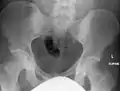

The radiographic appearance of osteopoikilosis on an X-ray is characterized by a pattern of numerous white densities of similar size spread throughout all the bones. This is a systemic condition. It must be differentiated from blastic metastasis, which can also present radiographically as white densities interspersed throughout bone. Blastic metastasis tends to present with larger and more irregular densities in less of a uniform pattern. Another differentiating factor is age, with blastic metastasis mostly affecting older people, and osteopoikilosis being found in people 20 years of age and younger.

The distribution is variable, though it does not tend to affect the ribs, spine, or skull.[2]